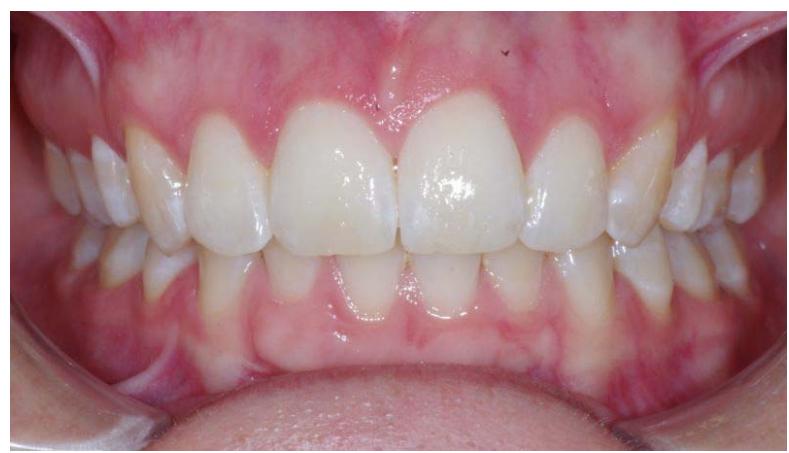

#### Examen endobuccal

L'examen endobuccal montre une supraclusion incisive, une DDM et un sens transversal correct. Dans le sens sagittal, on note une classe Il dentaire.

Examen endobuccal